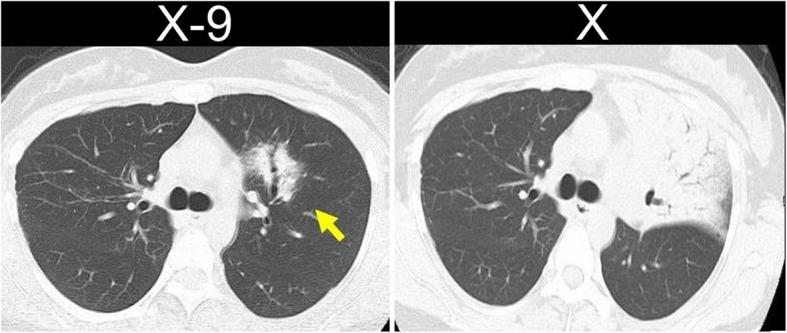

A 45-year-old woman was diagnosed with LIP and followed up for 9 years before being referred to our hospital due to an enlarging shadow on chest radiographs. The volume of the sample collected via bronchoscopy was too small to make a diagnosis, so the patient underwent surgery. The pathology results revealed diffuse proliferation of medium-sized lymphocytes filling the alveolar spaces, leading to a diagnosis of MALT lymphoma. After a thorough examination, no other lesions were found, confirming the diagnosis of EMZL of the lung, a primary pulmonary lymphoma (PPL). No postoperative treatment was administered after surgery; however, 2 years later, recurrence was detected in the stomach, and the patient underwent chemotherapy. Complete remission was achieved through chemotherapy, and the patient has been recurrence-free for 3 years since her treatment.

一名45岁女性被诊断为淋巴细胞间质性肺炎,并随访了9年,之后因胸部X线片上阴影增大而转诊至我院。通过支气管镜采集的样本量太小,无法做出诊断,因此患者接受了手术。病理结果显示中等大小淋巴细胞弥漫性增殖,充满肺泡腔,从而诊断为MALT淋巴瘤。经过全面检查,未发现其他病变,确诊为肺EMZL,即原发性肺淋巴瘤(PPL)。术后未进行任何治疗;然而,2年后,胃部出现复发,患者接受了化疗。化疗后实现了完全缓解,自治疗以来患者已无复发3年。